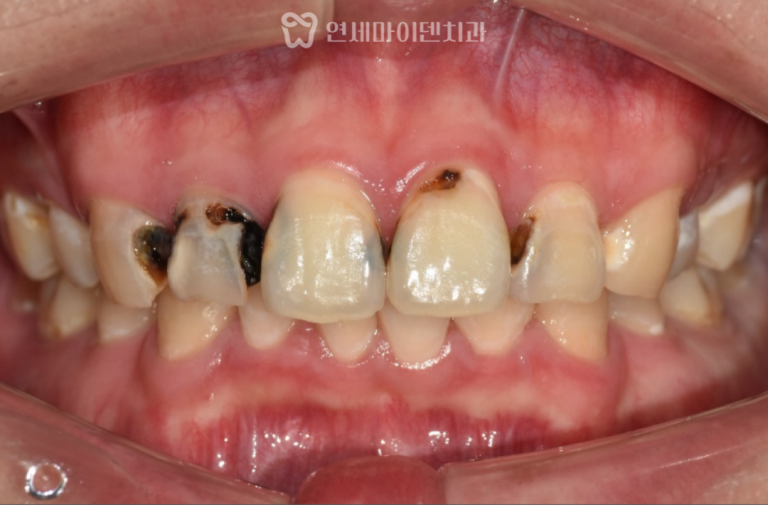

앞니 신경치료 3년 증례: 앞니 충치 오늘 소개해드릴 케이스는앞니에 심한 충치가 생긴 케이스입니다. 앞니는 단순히 기능적인…